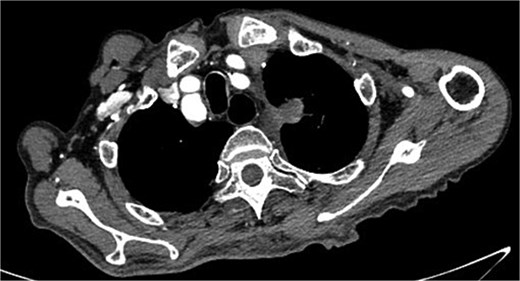

On March 1, 2024, the patient was readmitted for recurrent blood in phlegm. CTA revealed a type IV endoleak caused by membrane rupture. Angiography identified the endoleak at the stent graft junction (Fig. 8A). Controllable embolization coils were deployed to embolize the rupture. Post-surgery, symptoms disappeared (Fig. 8B).

(A) On March 1, 2024, the angiography showed endoleak (marked by arrows) at overlapping part of stent graft. (B) Dense embolization was performed on the residual breach of the stent graft membrane.